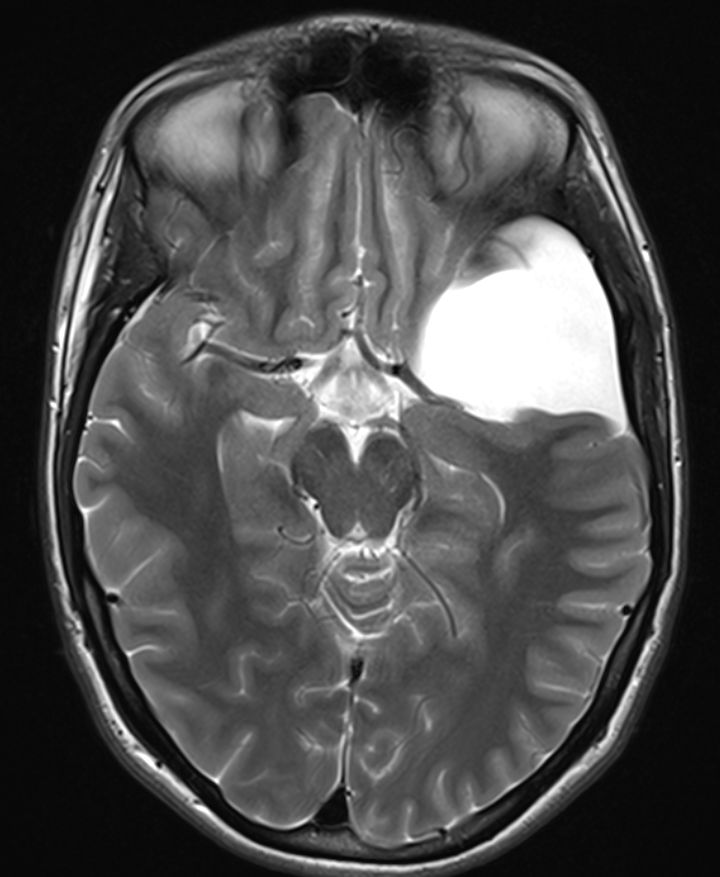

Arachnoidalzyste im MRI.

Axiale T2 Sequenz im MRI eines Patienten mit einer Galassi Typ 2 Arachnoidalzyste.